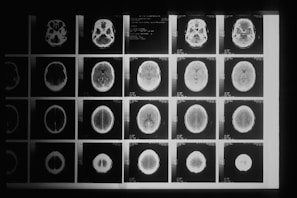

Image processing plays a vital role in modern medicine, especially in diagnosing and monitoring diseases through tools like MRI, CT, and ultrasound scans. It helps doctors visualize internal structures, detect abnormalities, and make accurate, timely decisions. However, as medical images become more complex and data-rich, traditional image processing methods face challenges in speed and efficiency. Quantum image processing offers a promising solution by using the principles of quantum computing to handle large and complex image data more effectively. Quantum algorithms can perform tasks like image enhancement, segmentation, and pattern recognition at much faster rates than classical systems. This is particularly useful for tumor detection, where early and accurate identification can significantly improve treatment outcomes. By enabling faster and more precise analysis, quantum image processing could revolutionize medical diagnostics in the near future.